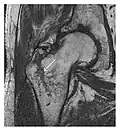

a

b

Figure 13: Partial osseous avulsion of the gluteal muscles at the greater trochanter in a 59-year-old man who presented with the right hip pain without a history of trauma. Lauenstein view and anteroposterior and radiographs (not shown) did not show an obvious fracture line or disruption of bony contours in the acetabulum or the right femoral neck. (a) Coronal T1-weighted MRI displays an incomplete fracture line extending partially from the greater trochanter (arrow). (b) Coronal short tau inversion recovery MRI shows heterogeneous hyperintensity in the same region (arrow) as well as hyperintensity within the gluteus medius and minimus muscles (arrowheads) consistent with tissue edema and hematoma.[1]